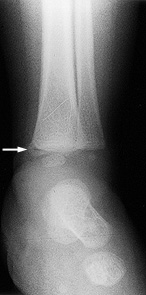

| Figure 1:Metaphyseal Bucket Handle Fracture | Figure 2:Posterior Rib Fracture |

Image used with permission from David Pressel, MD, PhD, Nemours/A.I. duPont Hospital for Children. |

Metaphyseal fractures are considered to be pathognomonic for abuse. These fractures are subtle findings on radiographs, often appearing as chips or fractures from the corner of the bone known as "bucket handle" fractures.37 (See Figure 1.) This type of fracture is particularly important to detect, as injury to the metaphyseal plate may limit future growth if not adequately treated in a timely manner.3

Rib fractures account for up to 27% of all abusive skeletal injuries45 and occur as a result of direct blows, as well as anteroposterior compression of the chest wall, such as occurs when holding and shaking an infant. Most abusive rib fractures are posterior and adjacent to the vertebral body, due to the leveraging of forces over the transverse process of the vertebra.37 (See Figure 2.) To diagnose these difficult-to-detect fractures, skeletal surveys are recommended in children younger than age 2 in whom abuse is suspected. Radionuclide bone scanning or repeat skeletal surveys within two weeks may detect new rib fractures and subtle long bone fractures not evident on skeletal survey.1,49